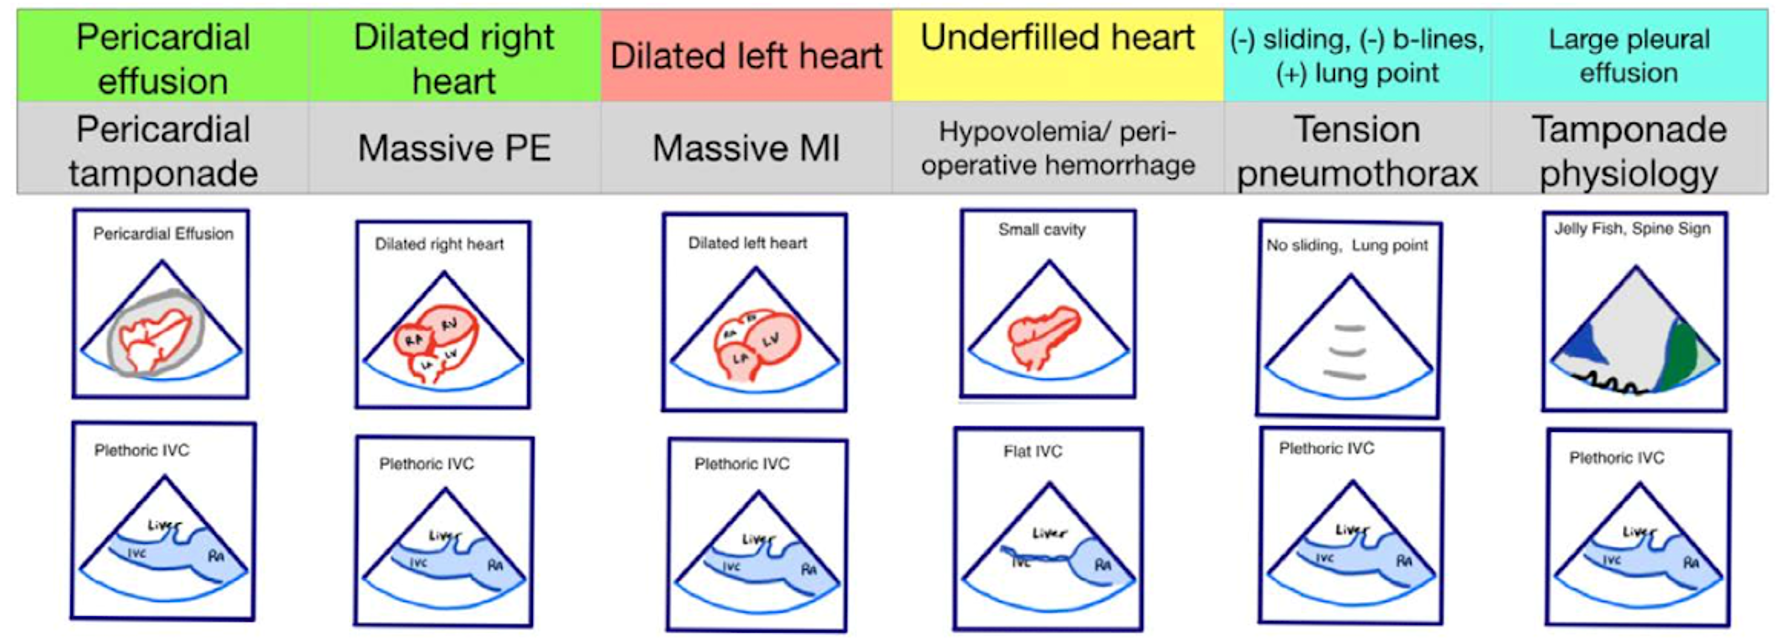

Figure 2. Pseudo-PEA phenotypes identified with EASy-ALS. The primary phenotypes to be identified with EASy-ALS are pericardial effusion, which may result in pericardial tamponade, dilated right heart, which pay occur with massive PE, dilated left heart, which may be seen with massive MI, and underfilled heart, which is associated with hypovolemia. Extracardiac views may be obtained as well; these include IVC ultrasound to assess volume status and RV filling pressure and lung ultrasound to assess for pleural effusion or tension pneumothorax. (Courtesy of N. Bughrara, MD, Albany, NY). EASy-ALS indicates echocardiographic assessment using subcostal-only view in advanced cardiac life support; IVC, inferior vena cava; MI, myocardial infarction; PE, pulmonary embolism; PEA, pulseless electrical activity; RA, right atrium; RV, right ventricular.

The responding resident is alerted to an acutely decompensating patient in the SICU or medical or surgical ward by direct call from the primary service or by overhead Code Blue page. On arrival, the resident prepares to serve as a sonographer and complete an EASy-ALS exam. The ultrasound probe is placed in the subcostal window before the pulse/rhythm check without obstructing chest compressions. The code leader, a senior primary care team provider, is responsible for holding and resuming chest compressions. The code leader assigns a nurse to count down 10 seconds during the pulse/rhythm check; this is standard at our institution. After resumption of chest compressions, the resident interprets recorded images and communicates findings to the code leader. The primary phenotypes (Figure 2) to be identified are cardiac standstill (see Video 1), pericardial effusion (Video 2), dilated right ventricle (RV) (Video 5), dilated left ventricle (LV) (Video 6), and underfilled heart (Video 7). The resident can obtain extracardiac views (such as the subcostal IVC View, Video 3), between pulse/rhythm checks.